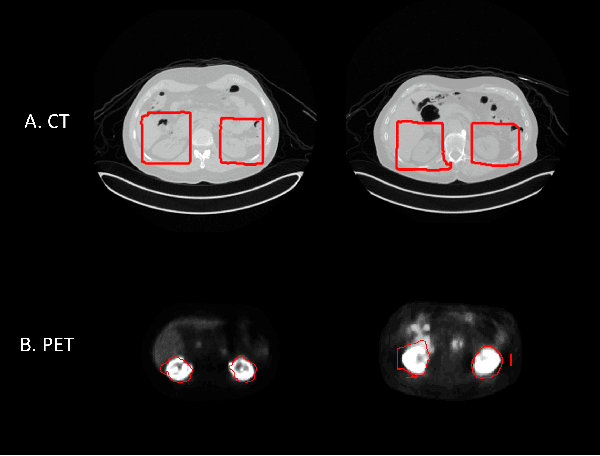

Abstract:Federated learning is increasingly being explored in the field of medical imaging to train deep learning models on large scale datasets distributed across different data centers while preserving privacy by avoiding the need to transfer sensitive patient information. In this manuscript, we explore federated learning in a multi-domain, multi-task setting wherein different participating nodes may contain datasets sourced from different domains and are trained to solve different tasks. We evaluated cross-domain federated learning for the tasks of object detection and segmentation across two different experimental settings: multi-modal and multi-organ. The result from our experiments on cross-domain federated learning framework were very encouraging with an overlap similarity of 0.79 for organ localization and 0.65 for lesion segmentation. Our results demonstrate the potential of federated learning in developing multi-domain, multi-task deep learning models without sharing data from different domains.